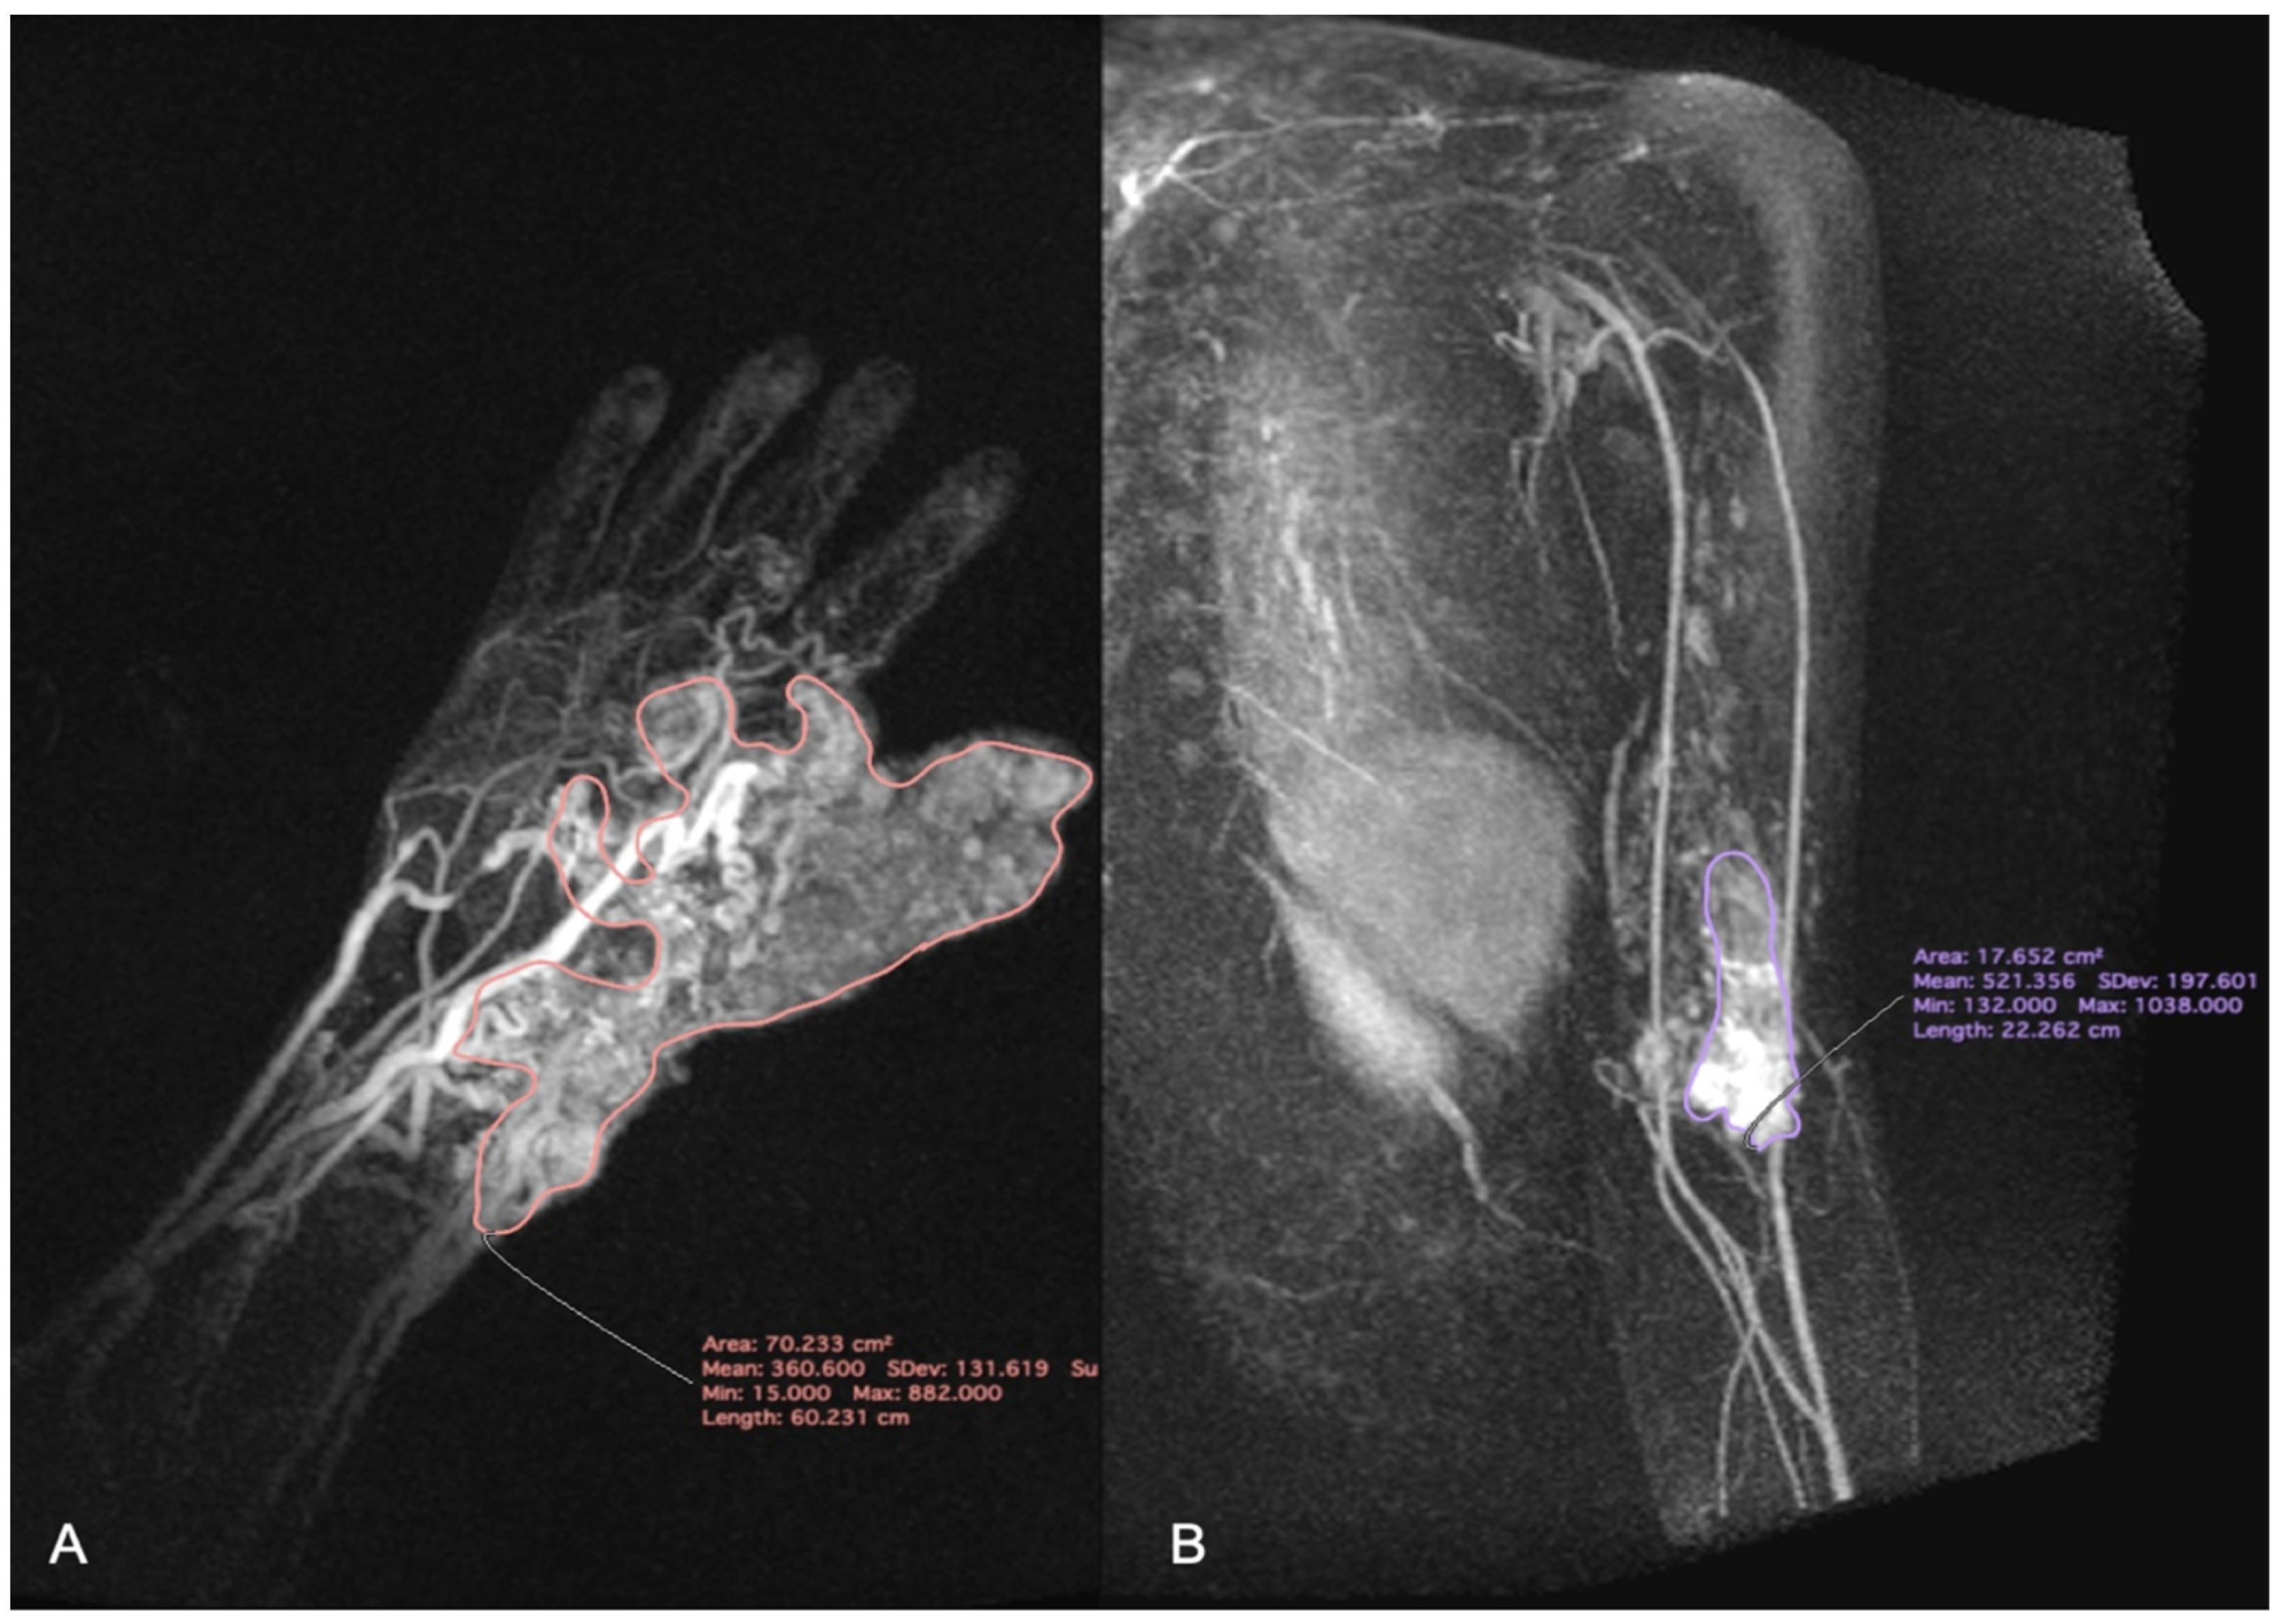

Then, the hemodynamic characteristic of VM was analyzed using TWIST maximum intensity projection (MIP) images. MIP images are obtained by projecting the voxel with the highest attenuation value on every view throughout the 3D image onto the 2D image. This method allows to display contrast-filled vessels preferentially and to get reconstructions similar to images obtained using the DSA [12]. The appropriate software (MeanCurve, Siemens Healthcare, Erlangen, Germany) was delivered by the workstation producer. First, the scan with the largest size of VM was chosen. The region of interest (ROI) was carefully, manually placed by the radiologist to contain the whole perimeter of the VM, as presented on Figure 2. Then it was duplicated on the rest of the scans. The signal intensity (SI) values inside all of the ROIs were measured and plotted versus the time of delay after contrast injection. The corresponding time intensity curve was calculated, as shown in Figure 3.

Figure 2. Time-resolved magnetic resonance angiography with interleaved stochastic trajectory (TWIST) maximum intensity projection (MIP) images. Vascular malformations (VMs) with the corresponding regions of interest (ROIs). (A) VM of the hand and wrist; (B) VM of the arm.